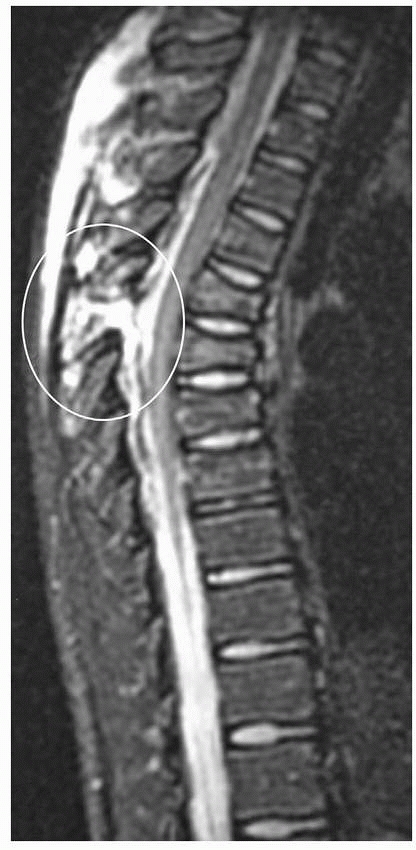

MRI is extremely sensitive and, given the brightness of edema fluid on

T2 images, may be overinterpreted. A study correlating MRI and

intraoperative surgical findings, however, demonstrated high levels of

both sensitivity and specificity in the MRI evaluation of posterior

soft-tissue injuries (Fig. 19-2).39

FIGURE 19-2

This sagittal MRI demonstrates marked increased signal in the posterior ligamentous complex. Anteriorly a loss of height at the vertebra can be seen, suggesting a three-column spinal injury. |